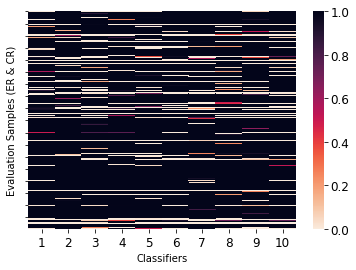

Despite being trained with the same dataset, upon plotting the predictions of each classifier for ER and CR evaluation samples in a heatmap (Figure 4), we observe that the classifiers often disagree. Therefore initializing each network using a unique seed value and stochastic sampling are a sufficient condition for convergence upon different optima. We observe that networks having different strengths can enable the construction of a diverse dataset during automatic labelling. We assign positive (containing anomalies) and negative (anomaly-free) labels using strict and lenient voting conditions, respectively, with the following intuition:

We use the FC-GANs based saliency maps to measure the agreement between classifiers under lenient voting conditions. A positive label is assigned to samples only when classifiers predict with above certainty that a vial is positive, and with a median pairwise distance between saliency maps that is less than . We chose these values by applying the lenient voting condition to a set of samples derived from anomaly free vials that were previously not included in the training or evaluation sets. This allows us to keep the number of false-positives to , while assigning positive labels to ( of) unlabelled samples. We subsequently use the strict labelling condition to obtain an additional negative samples. Prior to automatically assigning labels we exclude samples from the less indicative frame ranges, only keeping sequences starting at . We subsequently augment our dataset, adding self-training samples to our 14,000 hand-labelled samples, and train an additional ten randomly initialized 3D-ConvNets.